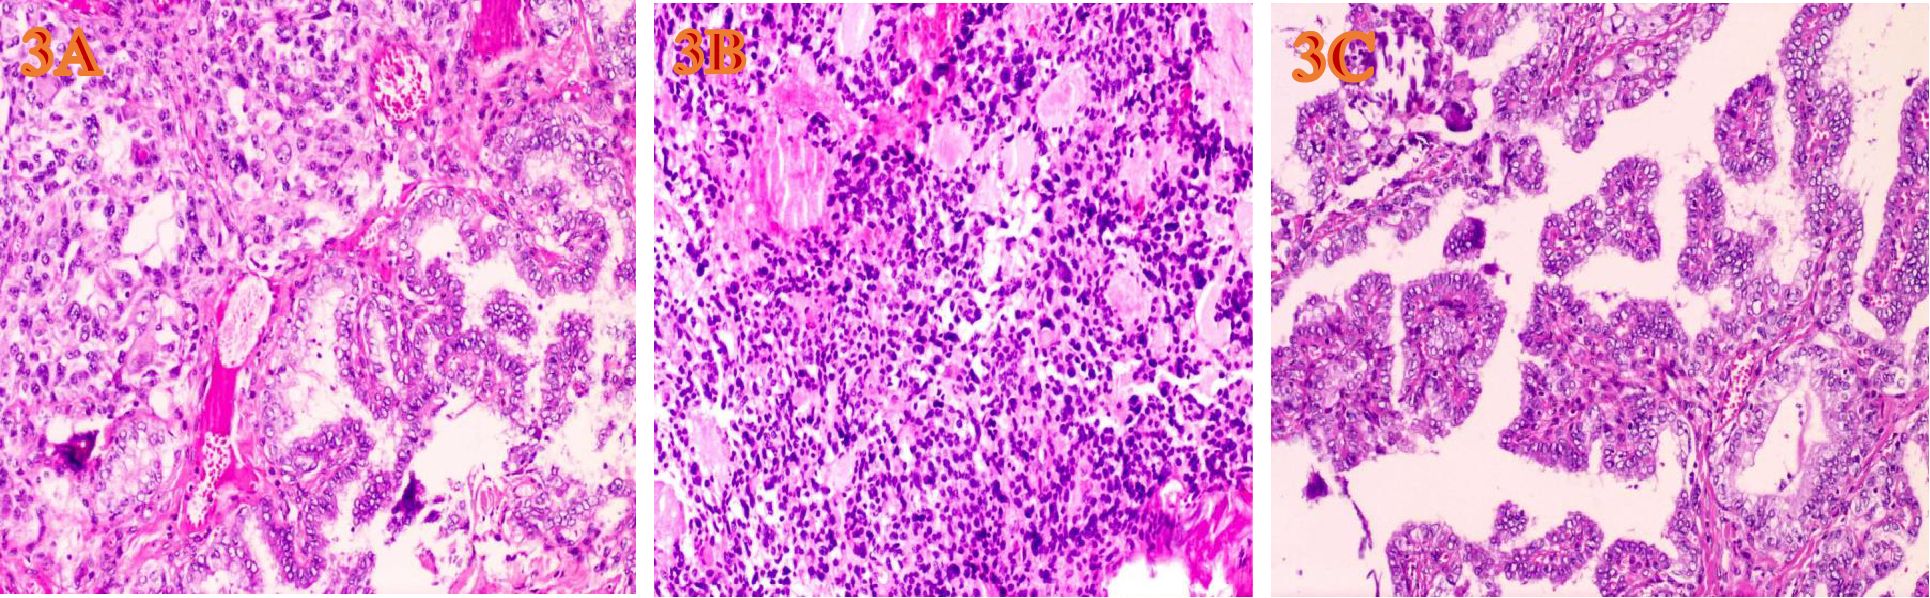

Figure 3

HE-stained microscopic images of tumors(H&E, ×200, magnification. (A) Under the microscope of MMPTC HE, MTC and PTC are interwoven. (B) The PTC cells are closely arranged, the cytoplasm is ground-glass-like, the nuclei are round or oval, and nuclear overlap, nuclear grooves and intranuclear pseudoinclusions can be seen. (C) The MTC cells have diverse shapes, including round, oval, and polygonal. Abnormal large cells and binucleated or multinucleated cells are observed. The nuclei are of varying sizes, with irregular nuclear membranes. The nuclear chromatin is granular (salt and pepper-like), and the nucleoli are prominent.